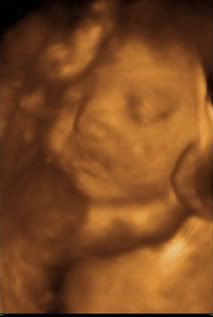

Today, we had breakfast... not the best I have had but it was food and then headed to the ultrasound... Baby A (I am calling her AJ) didn't really want to cooperate but we did manage to get some cute snap shots of her face... and interestingly... she has big ole lips!! Angelina Jole lips?!?! I call them ED lips.. (egg donor lips!! haha) AJ is just beautiful and I can't wait to meet her!!